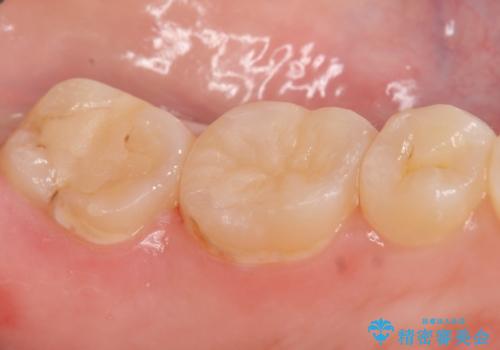

検査の結果左下6が虫歯になっていたため、セラミックインレーによる修復を行いました。

当院のセラミックインレーはemaxという強度と審美性に優れた材料を使用しています。

またプレス方式でインレーを製作しているため、削り出しで製作するCADCAMより優れた適合性も持ち合わせており、虫歯が再発しにくい修復物です。